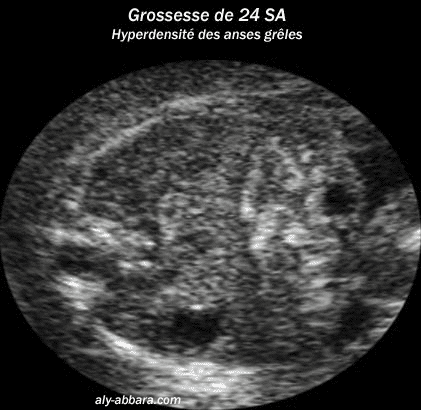

Grossesse de 24 semaines

d'aménorrhée avec la mise en évidence d'une hyperdensité

(hyperéchogénicité) des intestins grêles

Ce signe (avec d'autres signes

échographiques) a été associé chez ce ftus

d'une triploïdie 69, XXX.